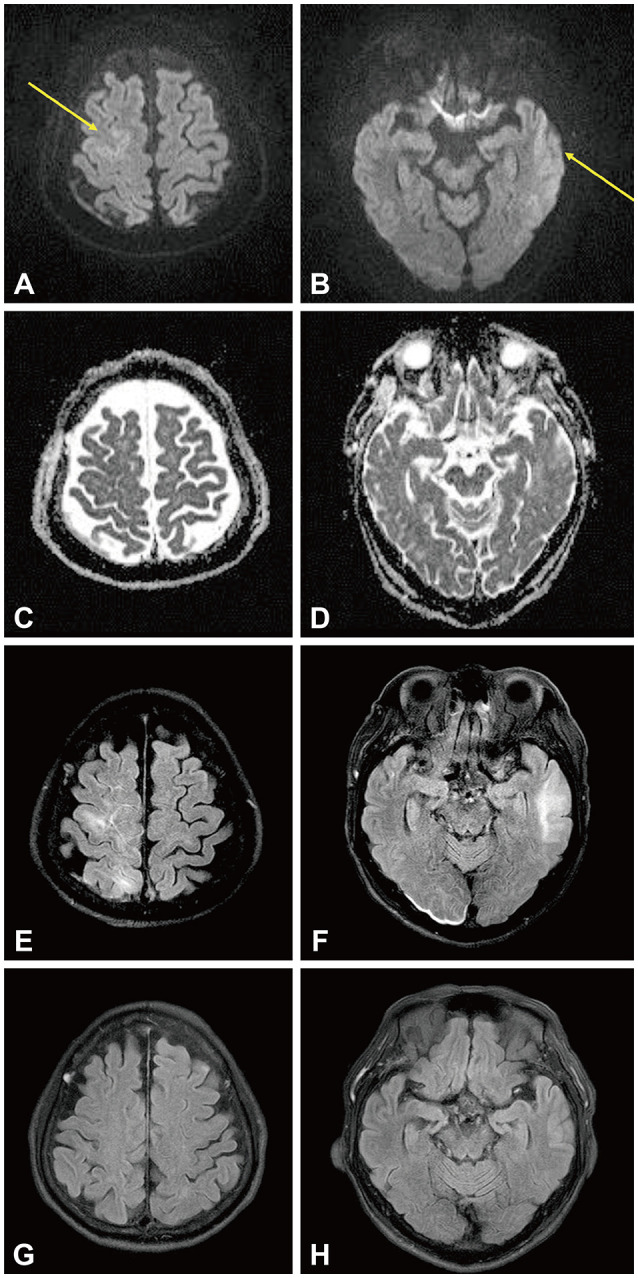

Refractory Status Epilepticus Associated With Dialysis Disequilibrium Syndrome.